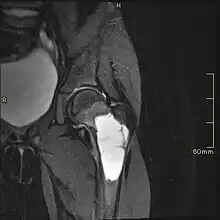

MRI

Magnetic resonance imaging (MRI) is used to identify the precise location of the cyst, to see how aggressive the disease is, and to determine the actual shape and size.[4] The MRI uses a combination of magnets and radio-frequencies to produce various detailed, computerized images of the cyst and its surrounding body structures.[4]